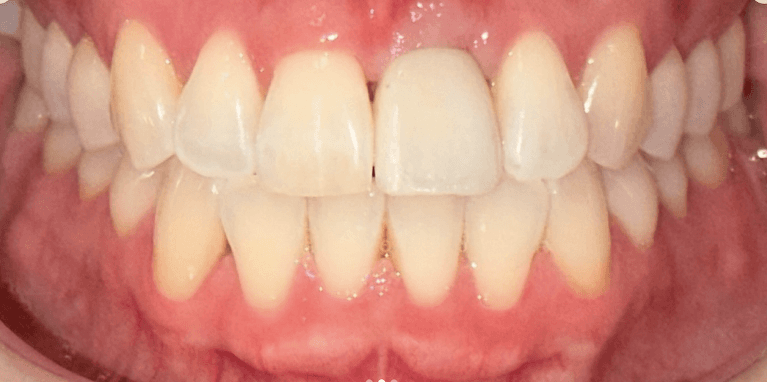

Upper & Lower, All on 4 fixed implant teeth with finals. Patient went home with temp fixed teeth the same day.